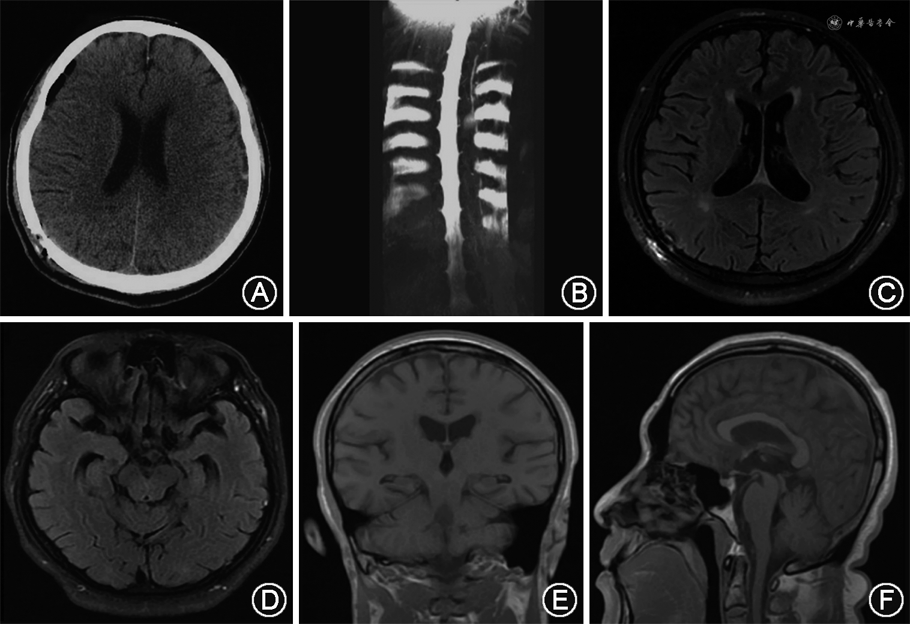

术后2 d患者直立性头痛消失,复查头颅CT未见新鲜硬膜下血肿(图2A),水成像可见硬脊膜外积液和神经根周围积液消失(图2B)。2021年1月9日,随访时患者复查头颅磁共振成像可见双侧SDH吸收,脑室及脑干受压缓解(图2C~F),至今随访5个月,头痛未再复发。